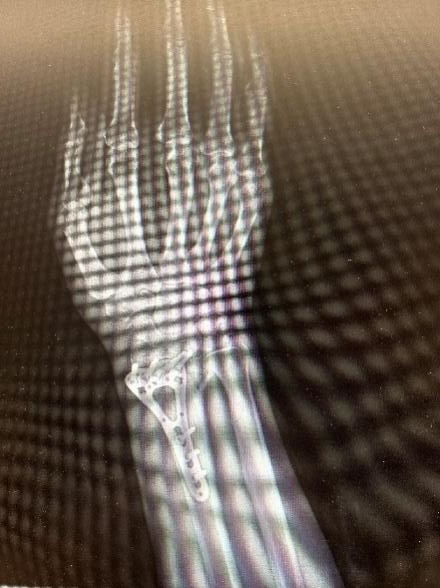

10月3日,60岁的陆女士(化名)滑倒后右手撑地,16:30入院就诊,顾晓娟医师团队诊断为:右尺桡骨骨折,充分评估后,22:00开始手术,1小时后返回病房。